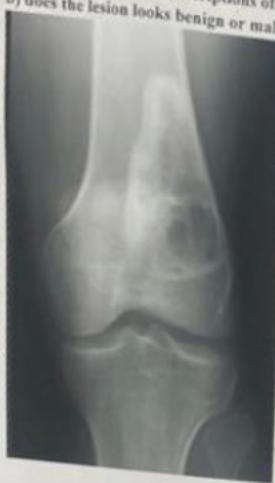

Examination of the knee

Knee Exam

| Item | Procedure | Purpose/ Indication … | Attachment Links | Positive Finding/Interpretation |

| Look | Compare both limbs, Skin, Muscle bulk, bony landmarks, hair distribution | Assess symmetry, signs of trauma, inflammation, muscle atrophy, structural changes | Visual examples - Skin, Muscle, Bone, Joint: ![]() ![]() ![]() ![]() ![]() ![]() | Swelling, scars, discoloration, hair changes, muscle wasting, bony protrusions, angulation, redness |

| Anatomic Examination: Joint assessment | Assess for swelling, effusion, crepitation, and synovial thickening | Joint Assessment: ![]() | Presence of swelling, effusion, crepitation, synovial thickening, joint line tenderness | |